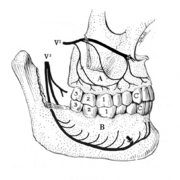

A tooth is composed of an outer shell of calcified hard tissues (from hardest to softest: enamel, dentin, and cementum), and an inner soft tissue core (the pulp system), which contains nerves and blood vessels. The visible parts of the teeth in the mouth — the crowns (covered by enamel) — are anchored into the bone by the roots (covered by cementum). Underneath the cementum and enamel layers, dentin forms the bulk of the tooth and surrounds the pulp system. The part of the pulp inside the crown is the pulp chamber, and the central soft tissue nutrient canals within each root are root canals, exiting through one or more holes at the root end (apical foramen/foramina). The periodontal ligament connects the roots to the bony socket. The gingiva covers the alveolar processes, the tooth-bearing arches of the jaws.[41]:1–5

Pericoronitis is inflammation of the soft tissues surrounding the crown of a partially erupted tooth.[24] The lower wisdom tooth is the last tooth to erupt into the mouth, and is, therefore, more frequently impacted, or stuck, against the other teeth. This leaves the tooth partially erupted into the mouth, and there frequently is a flap of gum (an operculum), overlying the tooth. Bacteria and food debris accumulate beneath the operculum, which is an area that is difficult to keep clean because it is hidden and far back in the mouth. The opposing upper wisdom tooth also tends to have sharp cusps and over-erupt because it has no opposing tooth to bite into, and instead traumatizes the operculum further. Periodontitis and dental caries may develop on either the third or second molars, and chronic inflammation develops in the soft tissues. Chronic pericoronitis may not cause any pain, but an acute pericoronitis episode is often associated with pericoronal abscess formation. Typical signs and symptoms of a pericoronal abscess include severe, throbbing pain, which may radiate to adjacent areas in the head and neck,[20][25]:122 redness, swelling and tenderness of the gum over the tooth.[26]:220–222 There may be trismus (difficulty opening the mouth),[26]:220–222 facial swelling, and rubor (flushing) of the cheek that overlies the angle of the jaw.[20][25]:122 Persons typically develop pericoronitis in their late teens and early 20s,[27]:6 as this is the age that the wisdom teeth are erupting. Treatment for acute conditions includes cleaning the area under the operculum with an antiseptic solution, painkillers, and antibiotics if indicated. After the acute episode has been controlled, the definitive treatment is usually by tooth extraction or, less commonly, the soft tissue is removed (operculectomy). If the tooth is kept, good oral hygiene is required to keep the area free of debris to prevent recurrence of the infection.[20]:440–441